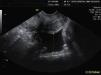

En la ecografía transvaginal se evidenciaron tres vesículas vitelinas con tres polos embrionarios de aproximadamente 3,5mm de LCN y con latidos cardíacos positivos, los tres en un mismo saco enclavado en tercio medio de trompa izquierda (fig. 1). Ambos anejos eran normales. El útero era regular, con la línea endometrial de 7,5mm espesor. En el saco de Douglas había cerca de 25mm de líquido libre (fig. 2).